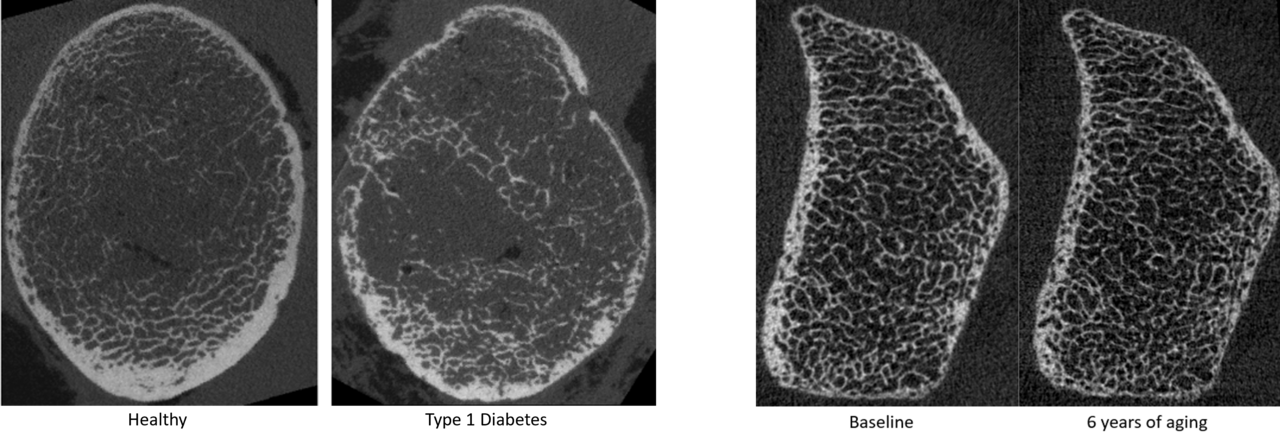

hrpqct images

High resolution peripheral QCT images comparing healthy and diabetic bone (left) and bone changes with aging (right)